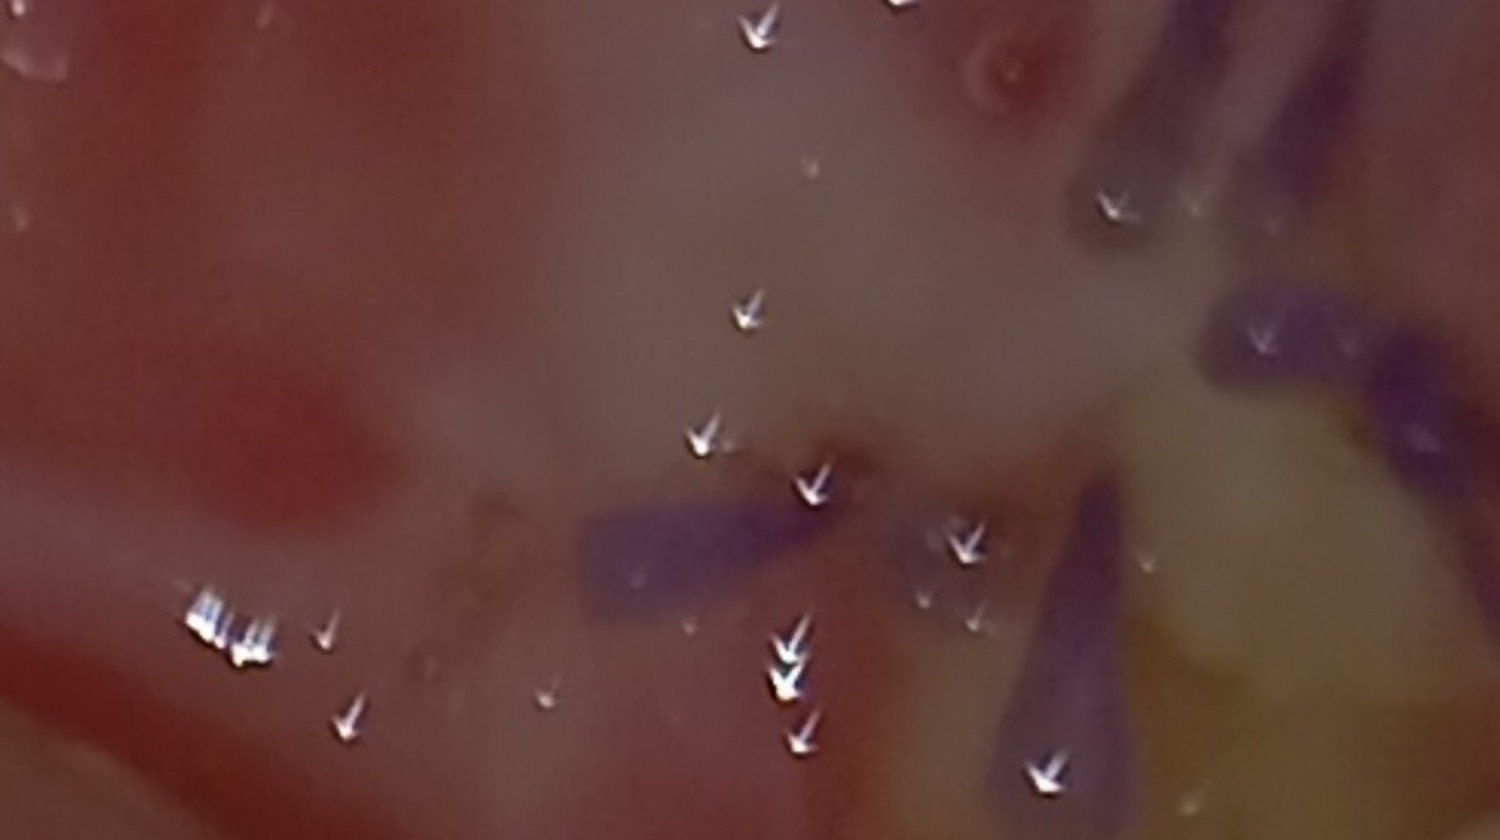

Witam,jestem po zabiegu operacyjnym wycięcia wyrostków rylcowatych czaszki.Schorzenie nazywa się Zespół Eagla,jest to bardzo rzadka choroba genetyczna,choruję na niá tylko około 0,4 % ludzi.Trafiło na mnie niestety.Pierwsze objawy miałam około 7 lat wcześniej,było to porażenie nerwów szyjnych i potężny ból.Potem pojawiły się problemy z barkiem,osłabieniem ręki,ma bardzo małá silę mięśniową co uniemożliwiło mi podjęcie pracy.Zdiagnozowanie było niemożliwe ponieważ świadomość lekarzy medycyny rodzinnej na temat tej choroby jest znikoma.Stopniowo narastała bezsenność i ciężka depresja,czułam się jak w potrzasku i chciałam odebrać sobie życie.Nie wiedziałam co się ze mną dzieje i na co choruję.Ten stan trwał długie i bardzo bardzo bolesne 7 lat.W tej chwili jestem już po operacji,która trwała około 5 godzin i powoli dochodzę do siebie ale część nerwów twarzowych i ręka,bark ucierpiały bardzo.Mogę używać tylko jednej ręki.Potrzebuję rehabilitacji,która kosztuje,leków,które wspomogą odbudowę uszkodzonych nerwów,drogich płukanek do jamy ustnej,które pomogą zagoić się głębokim ranom po wyciąganiu wyrostków i przede wszystkim pieniędzy na dojazdy do swojego profesora prowadzącego.To wszystko kosztuje a mnie odmówiono nawet renty z ZUS.Pracuje tylko mąż,więc bardzo proszę o wsparcie,żebym mogła jeszcze normalnie żyć.Te 7 lat odcisnęło na mnie piętno,chciałabym to wszystko wymazać z pamięci.